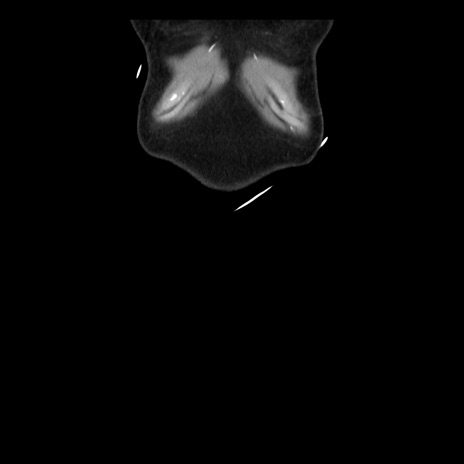

横断像